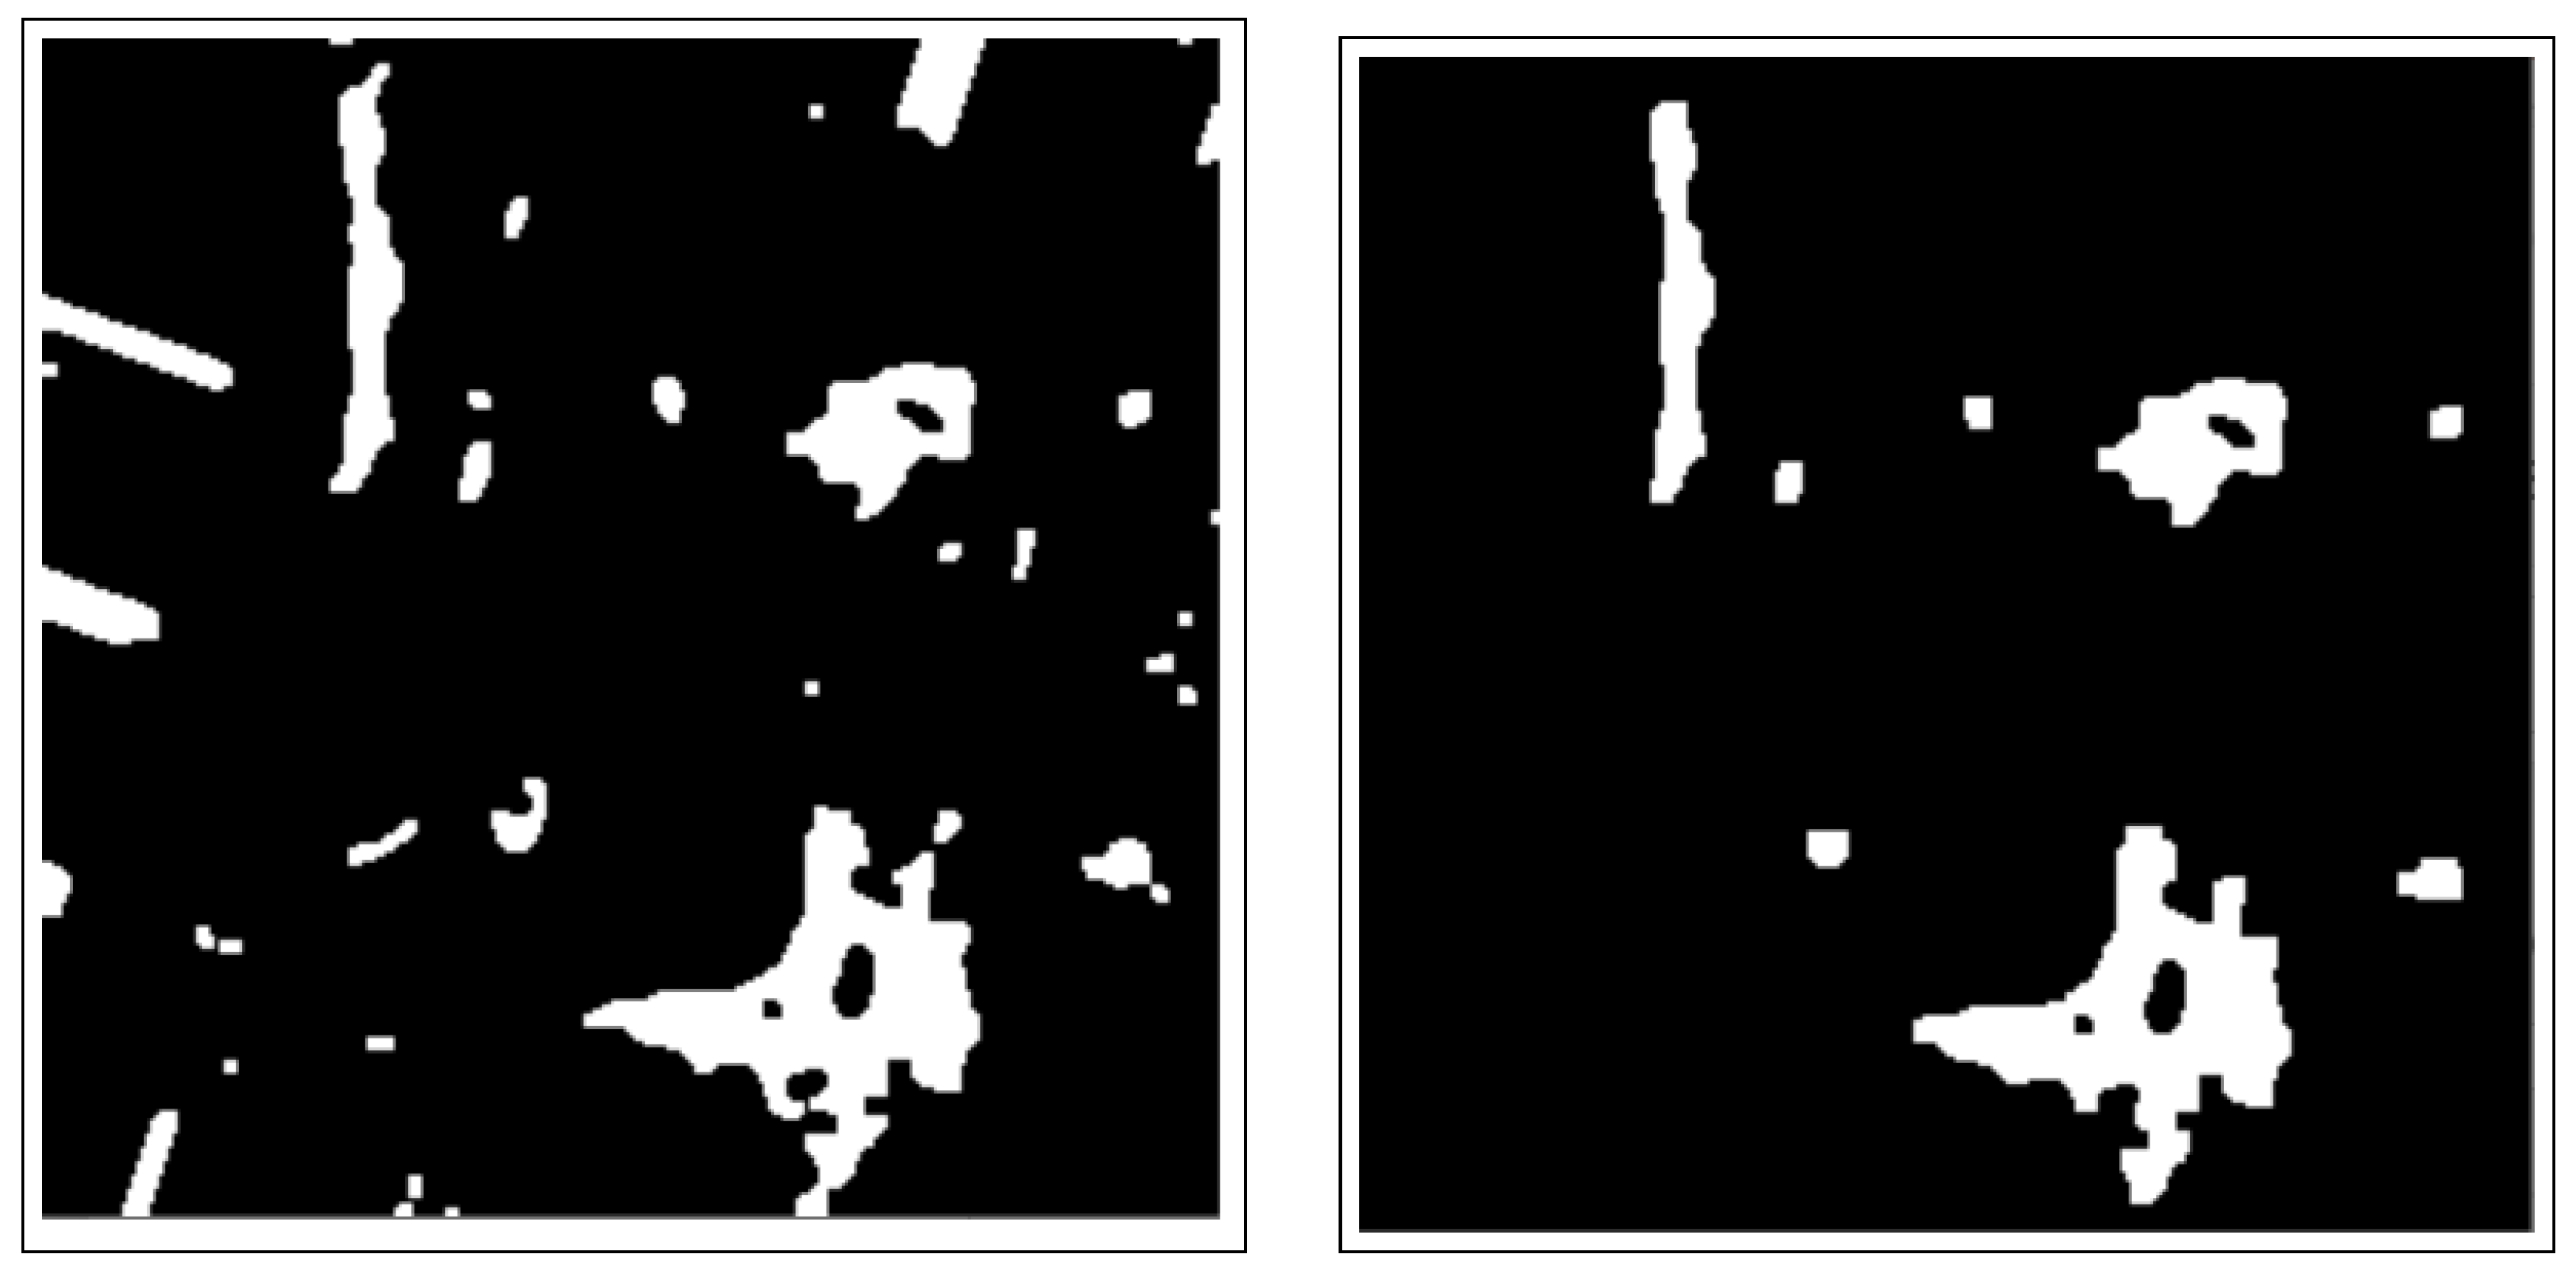

- The active contours method uses the obtained binary masks from the connected components analysis to highlight and isolate the edges/boundaries of ROIs. Further, the blob detection method is used to resolve undersegmentation from the previous step and identify BC lesions (blobs) from the previously obtained masked images.

3.3.2. Active Contours Segmentation